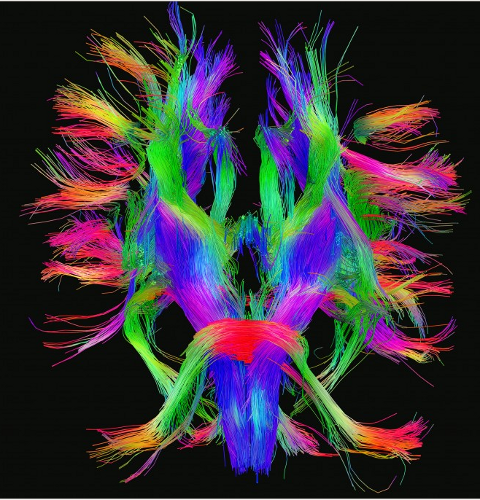

My interests span the information, physical and cognitive sciences, and their nexus, e.g. complexity.